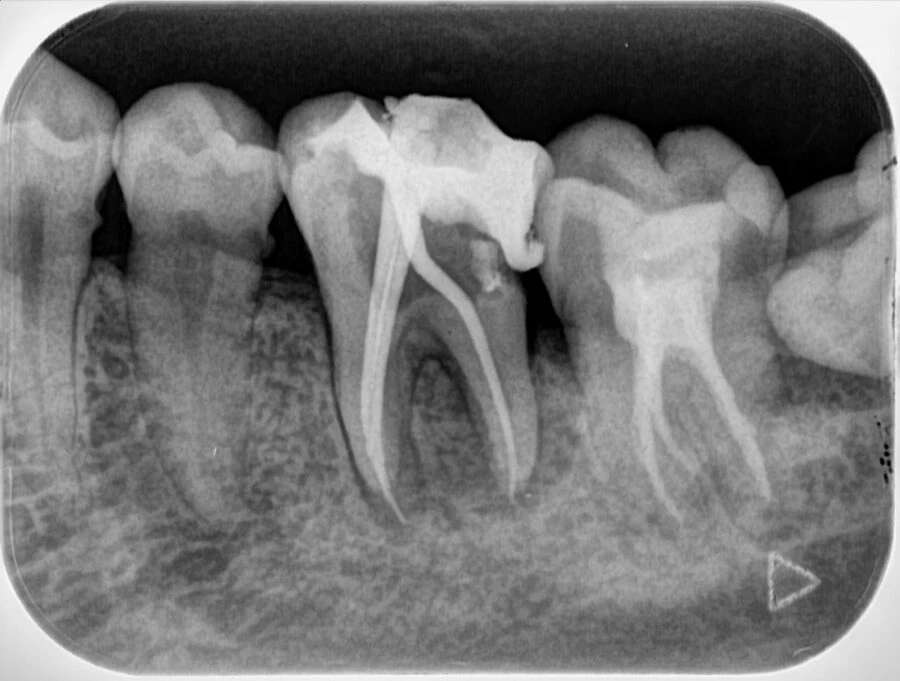

CRX-1000 sử dụng 4 tấm phim cảm biến với các kích thước khác nhau. Nhờ đó, việc đặt vào khoang miệng bệnh nhân trở nên dễ dàng và chính xác, cho chất lượng chụp X quang tốt nhất, tách rõ chân răng của bệnh nhân.

CRX-1000 sử dụng công nghệ MPPC đầu tiên trên thế giới sử dụng phương thức quét từ trên xuống dưới. Tấm phim được gắn tới đỉnh và quét một cách ổn định. Nhờ vậy, chất lượng hình ảnh rõ nét, chính xác. Giúp bác sĩ dễ dàng thuyết phục bệnh nhân chấp thuận phương án điều trị, phương án chi phí dễ dàng hơn rất nhiều.